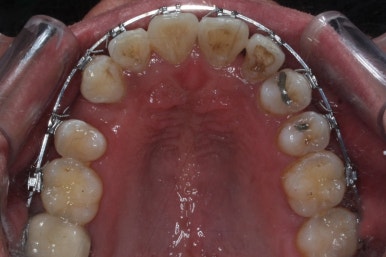

부산치아교정 키다리아저씨치과에 처음 내원 당시의 입안 모습입니다.

여러 가지 문제점이 있는데 하나씩 살펴볼게요.

치열이 많이 삐뚤하네요.

많이 삐뚠 상태에서 장기간 사용하다 보면 안좋은 방향으로 치아가 힘을 받게 되고 마모나 치아 목부분 패임이 심해집니다.

양치가 힘들어요. 양치가 힘들다 보니 세게 닦게 되고 치아 손상은 더 심해져요. 25세의 나이였는데 나이에 비해서 치아나이가 굉장히 많은거죠.